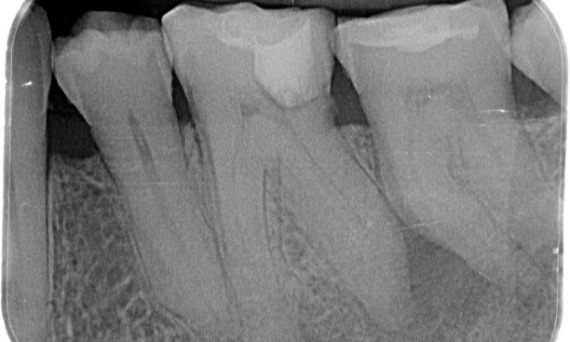

"Ein patienten- und behandlungsorientierter Erfolg." Dr. Cowie

Vorher: Periapikale Radioluzenz primär an der distalen Wurzel und Verlust der Lamina dura an der mesialen Wurzel.

Nachher: In diesem Fall wurde TruNatomy gewählt, um einen kariesfreien Ansatz zu ermöglichen und sich auf den Erhalt des perizervikalen Dentins zu konzentrieren, insbesondere auf der mesialen Seite, wo der Zahn eine minimalere Restauration aufwies.

Bath, UK